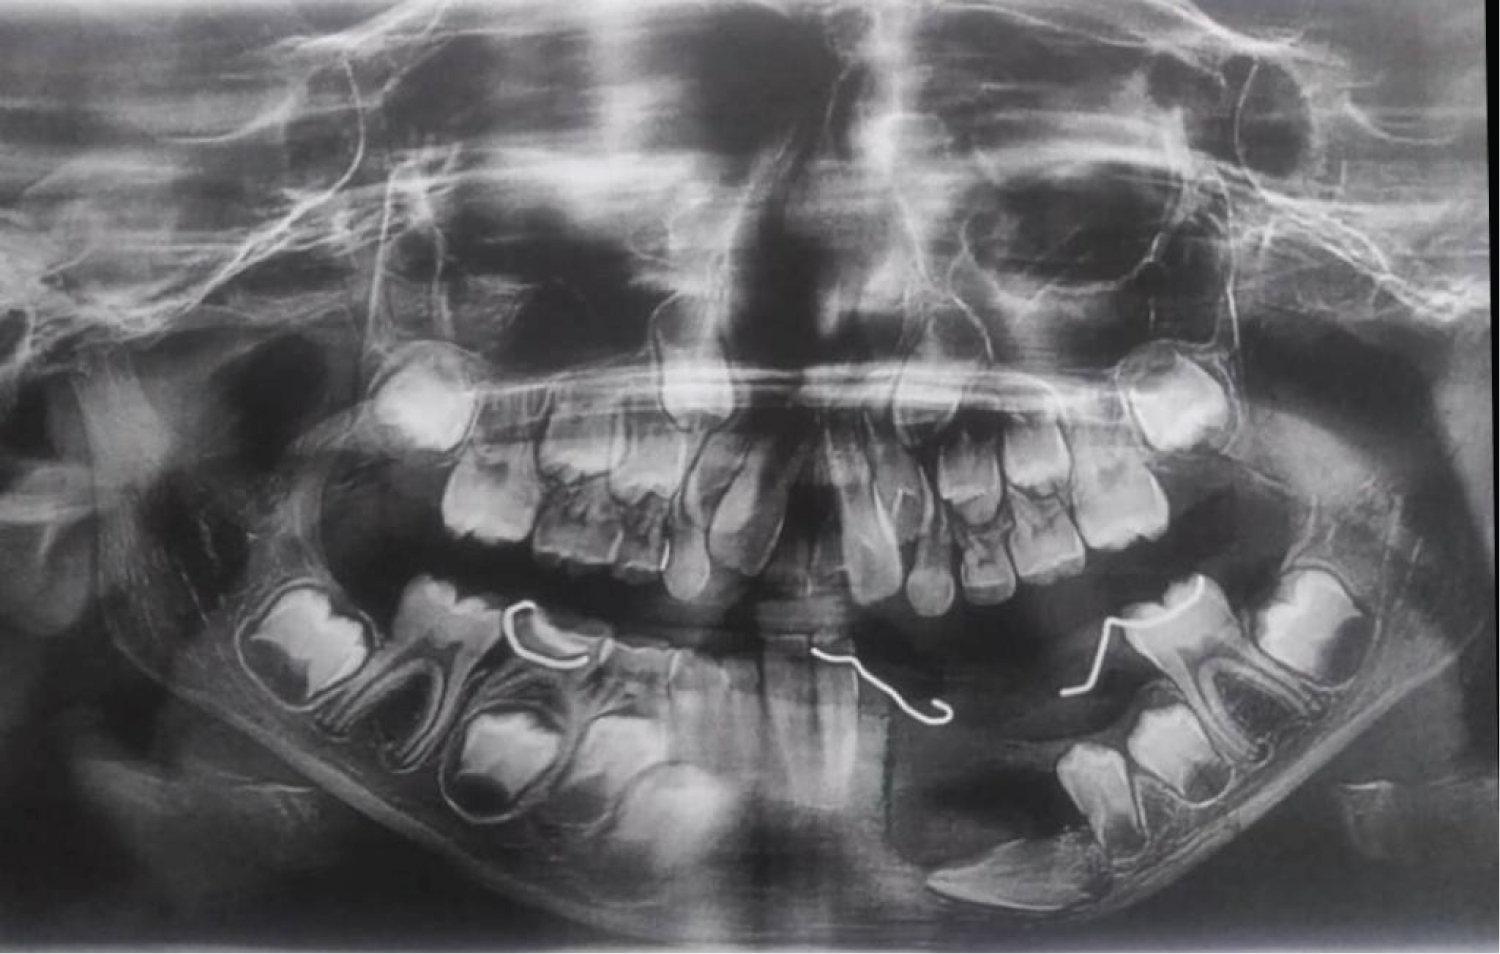

An 8-year-old African descent boy presented to the department of oral and maxillofacial surgery at Sharque Alnil Hospital complaining of swelling and lost teeth on the left side of the lower jaw for three weeks. No history of pain fever, loss of weight or night sweats. On examination, the face was symmetrical and no palpable lymph nodes. Intraorally, expansion of buccal and lingual cortices was seen on the left side of the lower jaw at the area of A, B, C, D, and E deciduous teeth with grade 2 motilities of A, B, C and D teeth and loss of tooth number D. no occlusal interference, no ulceration on the overlying mucosa. On the radiographic image (Figure 1 and Figure 2) Ill-defined radiolucency in the lower left side of the jaw extending from the first deciduous incisor to the second deciduous molar was evidence, permanent successors were within the tumor and were pushed downward and the lower border of the mandible was intact. In differential diagnosis, dentigerous or periapical cysts were thought. A biopsy was taken which microscopically showed interlacing bundles of oval cells with adjoining fibro-collagenous connective tissues and reactive bone trabeculae with no epithelial lining or granuloma or malignancy and that is revealed a benign spindle cell lesion. Further immunohistochemistry was recommended for verification and rule out of other possibilities and results were negative for desman, SMA, CD68, CD34 and S100, and results consistent with fibromatosis. After having to discuss the treatment plan with parents, the treatment plan was formulated. In order to preserve the permanent teeth, the young patient underwent conservative surgical curettage and extraction of loose deciduous teeth. A prosthesis was constructed to replace the extracted teeth and to cover the bony defect and the patient was subjected to periodic follow-up clinically and radio graphically. After 8 months postoperatively, the panoramic image did not show any evidence of recurrence. Moreover, the permanent teeth in the area of the surgery appeared to erupt uneventfully except the left lower canine (Figure 3). The patient is and closely observed to assure no recurrence and normal eruption of the permanent teeth.

Plain image of the affected bone shows well-defined radiolucent lesion which appears as unilocular or multilocular with partially sharp or diffuse border without sclerotic margins [10] which is in agree with our findings that exhibits a unilocular radiolucent lesion with ill-defined diffuse margins on the panoramic view, while the 3 D Con beam CT scan showed an obvious buccal and lingual cortexes defects. Floating teeth without alveolar bone support associated with root resorption is a common finding that agrees with our case. For precise assessment of the tumor which is mainly soft tissue, it is better to order MRI, to see the exact expansion of the tumor and it is also suitable for surgical planning [11].